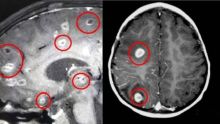

Bikin Merinding, Migrain Bertahun-tahun Ternyata Ada Cacing Pita di Otak Wanita Ini Kesehatan - 11 Oct 2020, 18:42